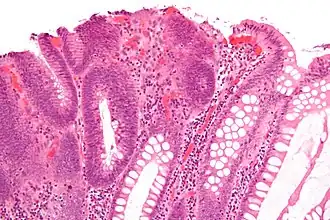

Hyperplastic polyp 0% No dysplasia.[10]

• Mucin-rich type: Serrated ("saw tooth") appearance, containing glands with star-shaped lumina.[11] Crypts that are elongated but straight, narrow and hyperchromatic at the base. All crypts reach to the muscularis mucosae.[11]

• Goblet cell-rich type: Elongated, fat crypts and little to no serration. Filled with goblet cells, extending to surface, which commonly has a tufted appearance.[11]